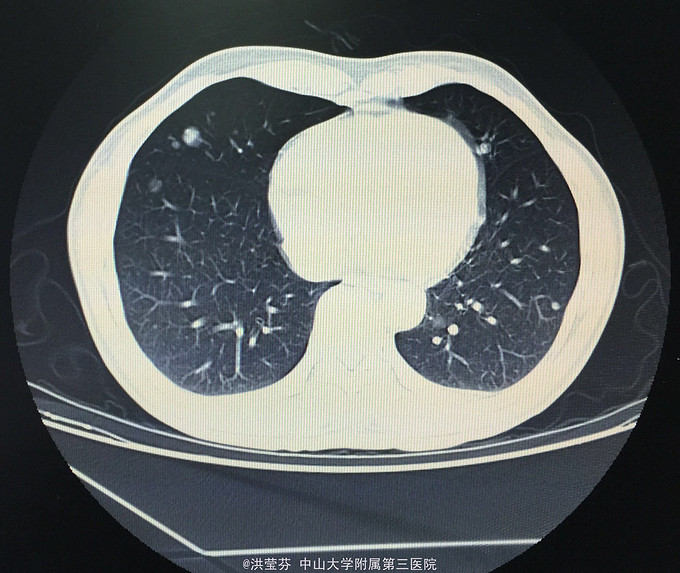

查体:KPS 60分,BSA 1.83m2,T 38.5℃,全身浅表淋巴结未触及明显肿大,胸壁可见浅表静脉曲张,呼吸急促,左下肺、右中下肺呼吸音明显减弱,其余肺野呼吸音促,可闻及少许实性啰音,心率110bpm,律齐,腹软,全腹无压痛、反跳痛,未扪及明显包块,肝脾肋下未触及,移动性浊音(——),肠鸣音正常,4次/分,双下肢无凹陷性水肿。 辅助检查:血常规无特殊,生化转氨酶稍升高,低钠低氯,CRP 227.9mg/L,凝血四项:Fib 8.14g/L。复查胸部CT提示:1.胸腺癌并纵膈淋巴结及双肺多发转移瘤,右心房、上腔静脉受侵并癌栓形成,病变较前进展。2.双肺炎症,以右肺为著。3.双侧胸腔及心包积液。上腹部CT提示:1.下腔静脉早显并肝表面多发侧支形成,考虑右心流出道阻塞所致;腹壁静脉曲张。头颅MR提示右侧颞叶强化灶,结合病史,考虑转移瘤,伴瘤灶少量出血可能,瘤周脑水肿。